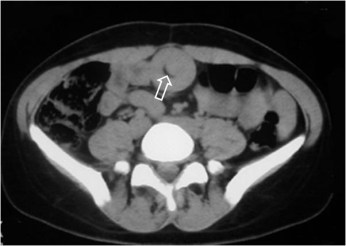

SIGNO DE LA SEMILUNA EN DONUTS

La invaginación intestinal provoca una imagen de donut o diana visible tanto por ecografía como por TC. La presencia de grasa mesentérica acompañando al asa invaginada, se ve como una semiluna (hiperecogénica en ecografía, hipodensa en TC) dentro de la imagen del donut.

Corte axial de TC de abdomen de otro paciente que muestra una semiluna con la densidad grasa del mesenterio en una invaginación ileo-ileal.

La referencia bibliográfica es un artículo de G del Pozo, J C Albillos y D Tejedor en Radiology: Intussusception: Us finfings with pathologic correlation. The crescent-in-doughnut sign. El abstract puede consultarse en: http://pubs.rsna.org/doi/abs/10.1148/radiology.199.3.8637988.